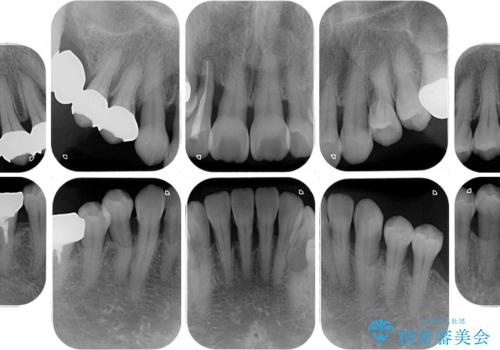

- 歯の欠損や歯肉からの出血などを気にして来院された患者様です。

診査の結果、歯周病であることが分かり、抜歯が必要な歯も見受けられました。

骨造成やインプラント、歯周外科、歯肉移植、矯正など、多くの処置を組み合わせて治療を行うこととしました。